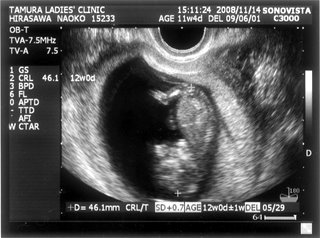

お腹の赤ちゃんは、今日で24週と4日。あっという間に7ヶ月突入です

![]() お腹もドンドン、食欲もドンドン出ていてあしたの4回目の検診コワーイ ![]() 妊娠発覚から三ヶ月半、なのにもう妊娠7ヶ月!頭がついていきません ![]() でも、毎日激しくなる胎動に感激している日々です ![]() 一回目の検診から4週後、2度目の検診に行ってきました。 2008年12月13日 赤ちゃんは15週と5日 ![]() 順調でした ![]() 左側から頭、胴体、足が写っていまーす ![]() 今回は4Dの機械も入り毎回撮影してくれるそうでーす ![]() 赤ちゃんは、ゴツゴツした背中だけを 見せ、顔はみせてくれませんでした~ ![]() それから4週後、3回目の検診。 2009年1月10日 赤ちゃんは19週と5日 ![]() 336gくらいになったようです ![]() 4D ようやく顔をみせてくれました ![]() かなりエイリアン ですが、フニュフニュ可愛かったです![]() 性別が わかりそうだったんですが、ソラ同様肝心なトコロをみせてくれませんでした ![]() もちろんどっちでもいいんですが、しりたーい ![]() 明日わかるかな ![]() ソラも赤ちゃんがテレビに映ったり、雑誌に載っていたり、 出かけ先で見かけたりすると、「ベイビー ![]() 」と大きな声で、何度も何度も興奮気味に言います ![]() 自分もまだまだ赤ちゃんなのに、「ベイビー」は自分より 小さくて可愛いものだと感じ始めているようです ![]() わたしは、一週間に1度だけ1歳になったばかりの 女の子を預かっています。 ソラは、その子が自分のオモチャを使うことに対して 少しイヤな気がしているようです ![]() 少し前までは「ドーゾー」と相手に有無を言わせず 何でも渡していたけど、どんどん自我が出てきているみたいですね~ そんな感じでオモチャを取り合いしながら、シェアすることも学んでいます。 でも女の子が寝ると、さすがに可愛いと思ったらしく、 頭をナデナデ、チュしていました ![]() 妊娠検査薬で妊娠反応がプラス |